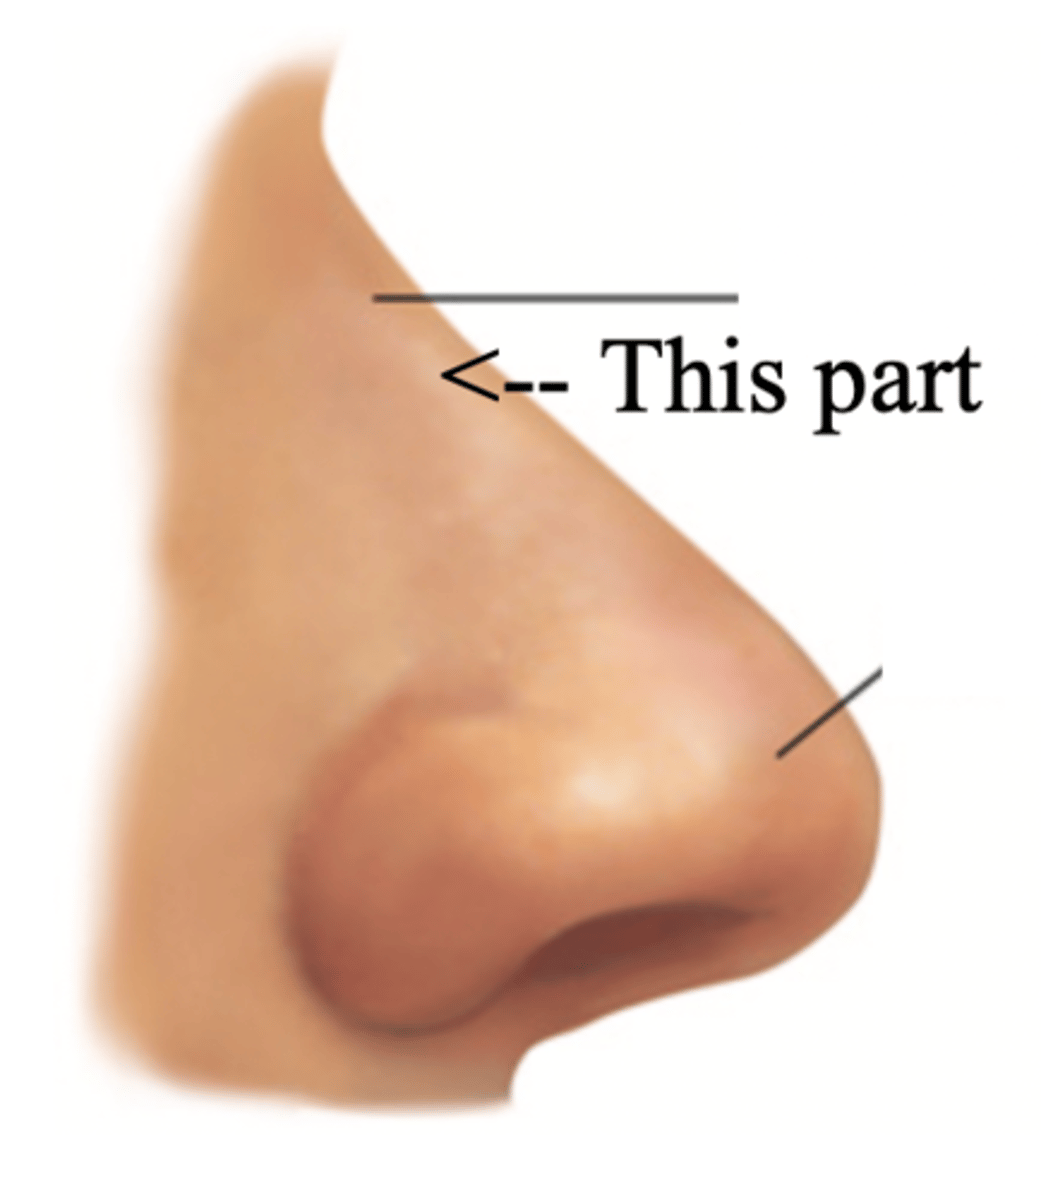

Bridge